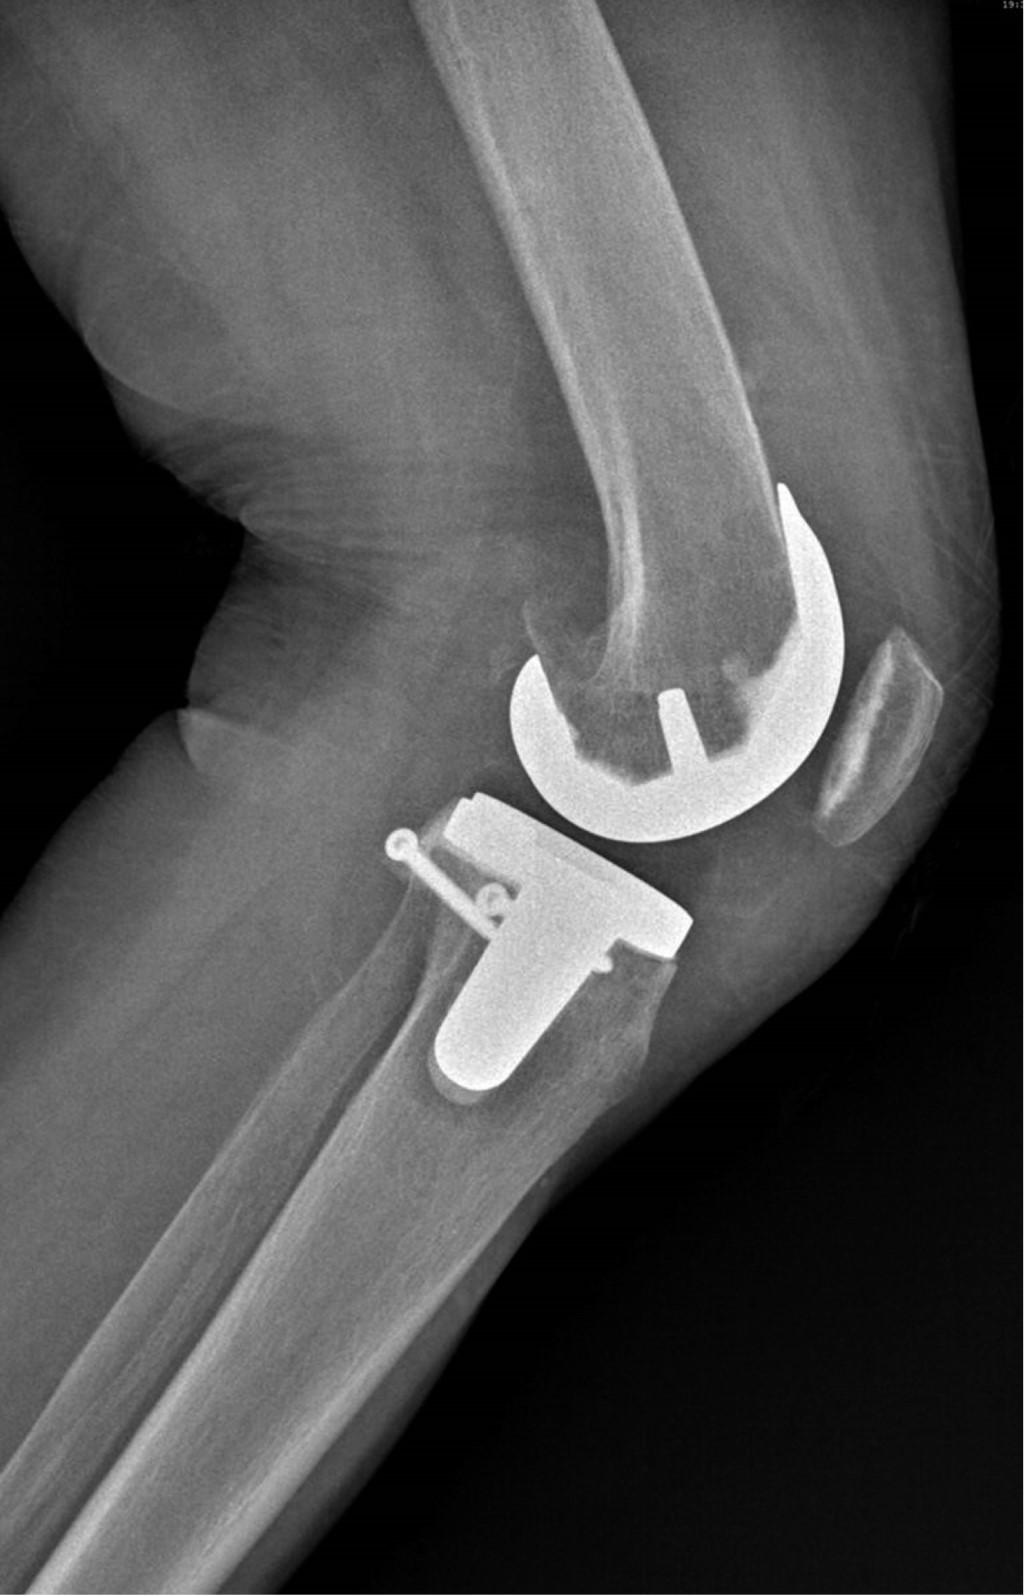

Se presenta caso de mujer de 62 años, dedicada al cuidado del hogar, con antecedente de presbiacusia, la cual acude a consulta externa por gonalgia bilateral, de predominio izquierdo, de siete años de evolución. A la exploración física se aprecia franca deformidad en varo en ambas rodillas (Figura 1), de mayor magnitud en lado izquierdo, con marcha independiente asistida con bastón, rango de movilidad activo con extensión de -5o, flexión de 85o, Ficat y cepillos positivos, cajones negativos y bostezo medial positivo, con limitación por dolor para las actividades de la vida diaria y dolor en EVA de 8. Se solicitan y revisan radiografías anteroposterior (Figura 2) y lateral (Figura 3) de ambas rodillas en bipedestación, encontrando gonartrosis bilateral Kellgreen & Lawrence IV, con defecto tibial medial en rodilla izquierda, por lo cual se le propone tratamiento quirúrgico con artroplastia total de rodilla izquierda posteroestabilizada, debido a la mayor sintomatología en dicho lado.

Figura 3

Figura 4